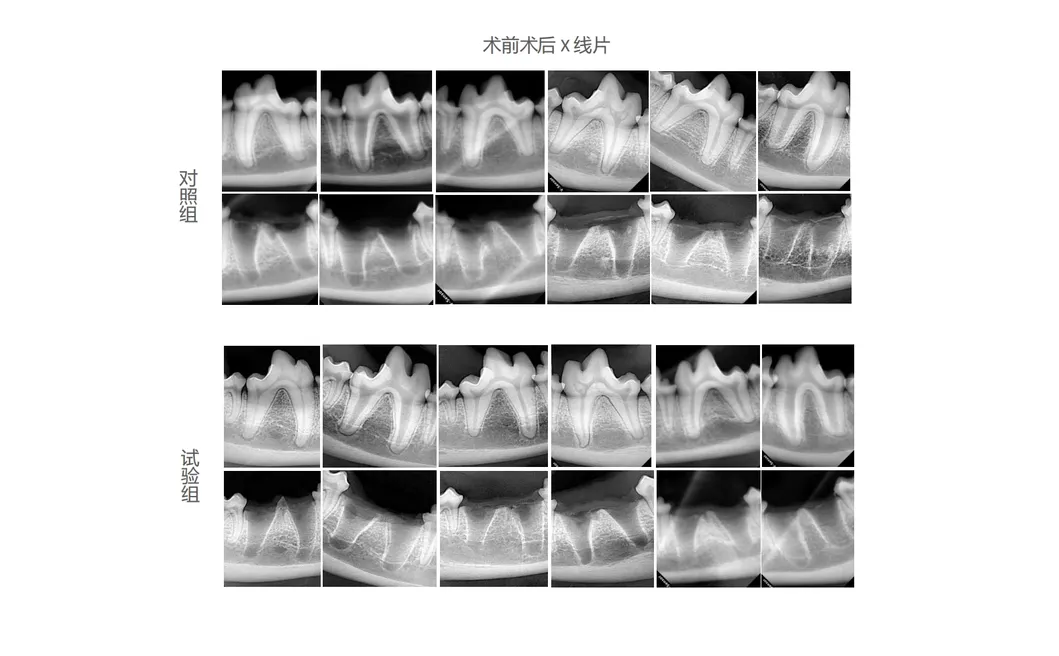

In this groundbreaking study, our team embarked on an exploration to unravel the unparalleled effectiveness of revolutionary dental tools, selecting dogs as the quintessential experimental subjects. The control group adhered to using conventional manual tooth extraction devices, while the treatment group utilized the state-of-the-art Golden Cudgel-Pneumatic Dental Elevator Kit. Researchers observed and documented critical factors such as physiological parameters, the incidence of intraoperative complications, the duration of extractions, and the degree of damage inflicted upon the extraction socket. The study delved into evaluating postoperative soft tissue healing processes, performing a thorough analysis of haematological data, and conducting comprehensive imaging and histological assessments.

Through rigorous experimentation and thorough analysis, the revolutionary Golden Cudgel - Pneumatic Dental Elevator Kit excels in the following critical areas: